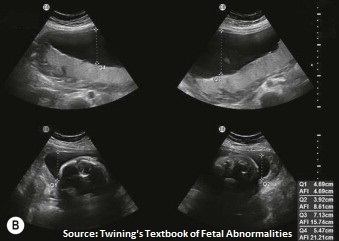

Amniotic Fluid

The amniotic fluid can be anechoic or have low level echoes (vernix). In order to obtaion the amniotic fluid index AFI, divide uterus into four quadrants via the linea alba and umbilicus , measure largest vertical pocket in each quadrant excluding cord.

An abundance of fluid is termed polyhydramnios, too little fluid is oligohydramnios